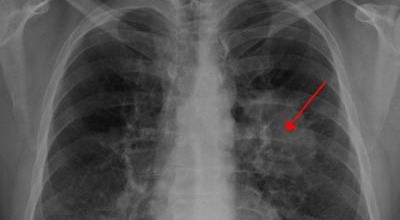

폐암은 폐에 생기는 악성 종양을 말합니다. 폐에서 직접 발생하는 원발성 폐암과, 다른 장기에서 전이되어 온 전이성 폐암으로 나눌 수 있어요. 전 세계적으로 매년 약 130만 명이 폐암으로 사망하는데, 이는 암으로 인한 사망 원인 중 가장 높은 비중을 차지하고 있습니다.

폐암 초기증상 ④ 가슴 통증

폐암 초기 증상 중 하나로 가슴 통증이 있습니다. 폐암 환자의 약 3분의 1 정도가 흉통을 호소하는데요, 이는 폐 가장자리 부분에 종양이 생기고, 그 종양이 암세포를 생성하며 흉벽과 흉막에 닿아 통증을 유발하기 때문입니다.

흉통은 여러 원인으로 발생할 수 있지만, 폐암에서 기인한 흉통은 지속적으로 쿡쿡 찌르는 듯한 느낌과 함께 가벼운 통증이 아닌 둔탁한 통증이 동반되는 경우가 많으니 주의가 필요합니다.

폐암 초기 증상으로는 혈담이 있습니다. 혈담은 쉽게 말해 가래에 피가 섞여 나오는 경우를 뜻합니다. 폐암이 폐 중앙부 기관지 근처에 위치할 경우 나타나는 혈담은 폐암 환자의 25% 이상이 경험하는 증상입니다. 만약 기침할 때 심한 가래나 혈담이 섞여 나온다면 즉시 병원을 방문하시길 권합니다.